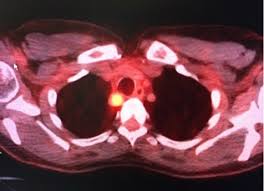

How Do You Know If A Cancer Has Spread / How Does Breast Cancer Show Up On A Pet Scan By Pet Ct Of Las Colinas Issuu : When cancer is said to be in stage 1, it means that cancer has spread to a nearby tissue but has not gone beyond.

How Do You Know If A Cancer Has Spread / How Does Breast Cancer Show Up On A Pet Scan By Pet Ct Of Las Colinas Issuu : When cancer is said to be in stage 1, it means that cancer has spread to a nearby tissue but has not gone beyond.. Symptoms of metastatic testicular cancer can include: Prostate cancer that has spread to the liver, intestines, or bones of the abdomen and pelvis can usually be found with a ct scan. For pancreatic cancer, we can barely connect with more risk factors than with family history and smoking. Breast cancer that has spread to the bones may cause: The symptoms of this metastasis may include drowsiness, confusion, headache, and weakness of an arm /leg.

It also tells if the cancer has spread to other parts of your body that are close by or farther away. In tmn staging, doctors also assign numbers after the letters t, m, n that explain how advanced your cancer. For pancreatic cancer, we can barely connect with more risk factors than with family history and smoking. When symptoms are present, they may include: The cancer has spread to a lymph node that measures more than 6 cm across.

The lower the number, the less the cancer has spread. Symptoms if cancer has spread to your lymph nodes lymph nodes are part of a system of tubes and glands in the body that filters body fluid and fights infection. The bone cancer stages are a crucial component when answering the question of how fast does bone cancer spread. It also tells if the cancer has spread to other parts of your body that are close by or farther away. Knowing the type of cancer and whether it has spread helps the health care team suggest a treatment plan. Cancer which has spread to the lymph nodes can sometimes be detected if the lymph nodes have become enlarged. The spread of cancer from where it started to another place is called metastasis. Metastasis means that cancer spreads to a different body part from where it started. That's why it's crucial to understand the early signs of bone cancer, and whether you have developed bone metastases or primary. Many colorectal cancers are likely to have spread from the site where they first formed to other parts of the body long before the original tumor can be detected by current screening tests, new study results suggest. Sudden bone pain, such as hip or back pain, which may feel similar to the discomfort associated with arthritis or exercise strain an increased risk of bone fractures that result from minimal trauma, such as a minor fall It also tells if the cancer has spread to other organs of your body that are close by or far away. How cancer spreads, shows how cancer cells can break off from the primary tumor in one organ, travel through a blood.